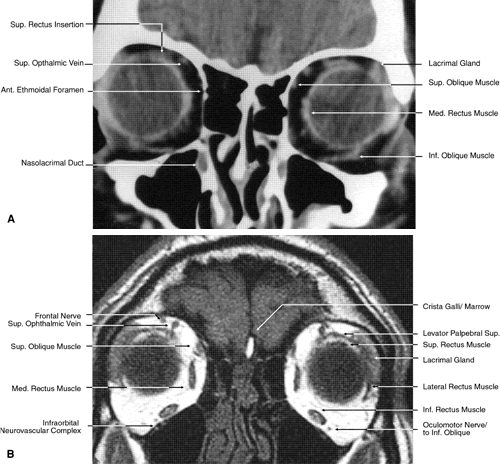

Fig. 17. Coronal images through anterior orbit. A. Computed tomography scan. B. T1-weighted magnetic resonance imaging.

Fig. 18. Coronal images through midglobe. A. Computed tomography scan. B. T1-weighted magnetic resonance imaging.

Fig. 19. Coronal images through midorbit posterior to the globe. A. Computed tomography scan.B. T1-weighted magnetic resonance imaging.

Fig. 20. Coronal images through orbital apex. A. Computed tomography scan. B. T1-weighted magnetic resonance imaging. C. Anatomic section of a cadaver head at the level of the orbital apex.